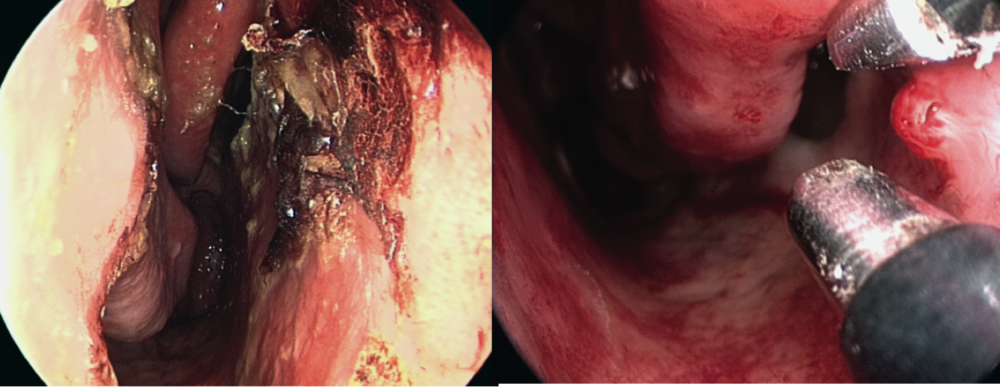

Imagen taponamiento anterior

Tratamiento Epistaxis posterior Taponamiento posterior Antibióticos Hospitalización 72 hr minimo

Imagen taponamiento posterior

Imagen Rapid-rino